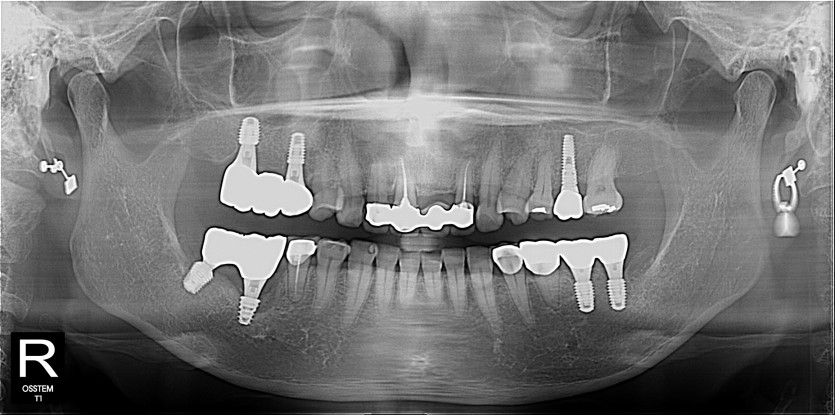

임플란트 사례